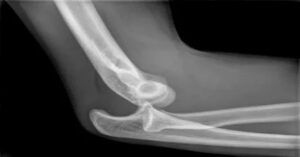

Bu çıkık, acil bir durumdur ve derhal müdahale gerektirir. İlk adımda, çıkık bölgeye baskı yapmaktan kaçınılmalı ve bölge hareket ettirilmemelidir. Acil servise başvurulması önerilir. Doktor, çıkık tanısını koymak için röntgen çeker. Röntgen, çıkık dışında herhangi bir kırık olup olmadığını da belirler. Bu işlem, tedavi planının doğru bir şekilde yapılabilmesi için önemlidir. Tedavide, çıkık yerine oturtulması gerekir. Bu işleme “redüksiyon” denir. Genellikle lokal anestezi veya genel anestezi altında yapılır. Çıkık, dikkatlice eski yerine yerleştirilir.